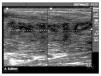

Se realizó de nuevo punción y aspiración dirigida. El cultivo y el antibiograma mostraron estafilococos coagulasa negativos sensibles al trimetoprim/sulfa-metoxazol. Tras 10 días de tratamiento el paciente estaba completamente asintomático, y a pesar de las imágenes ecográficas que se muestran en la figura 4, se le permitió volver a la competición.

Figura 4 Imagen hipoecoica de tejido cicatricial de reparación de 5 cm de eje mayor longitudinal en el músculo tensor de la fascia lata.